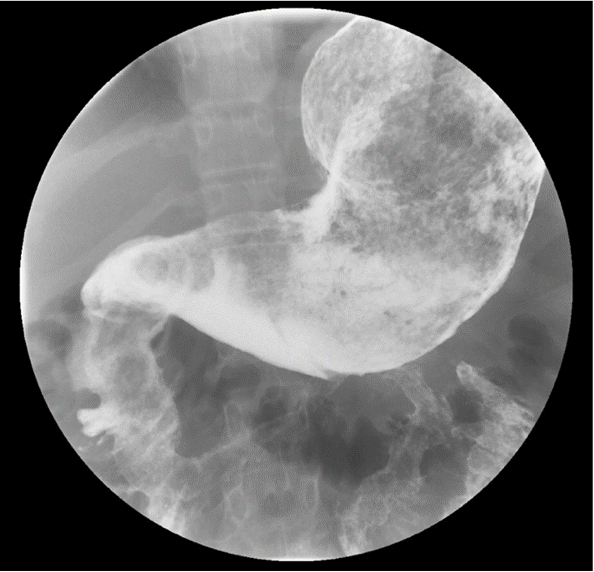

Diagnostic tests. A complete blood cell count showed a persistent moderate microcytic anemia with no leukocytosis or thrombocytosis. The sedimentation rate was elevated at 64 mm/h. Out of concern for new-onset inflammatory bowel disease, she was admitted. Given the history of vomiting and concern for stricture, an upper gastrointestinal contrast study was obtained, the results of which were notable a large filling defect extending from the stomach through the pylorus to the proximal jejunum, with features suggestive of a large trichobezoar (Figure 1).

Figure 1. Upper gastrointestinal contrast study showing a large filling defect in the stomach, duodenum, and proximal jejunum.